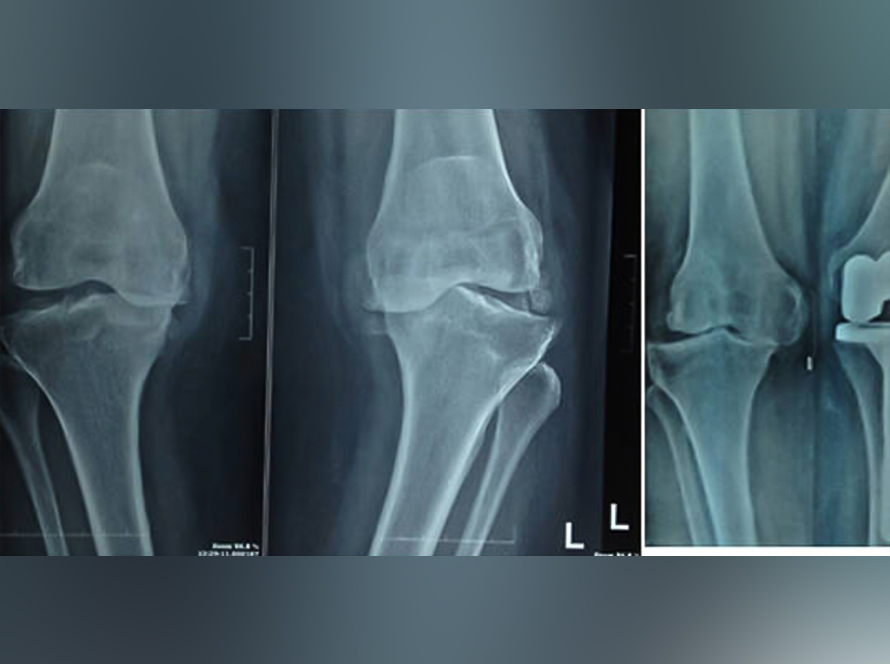

Eight Facts about Revision Knee Replacement

What Is Revision Knee Replacement? Procedure, Indications, and Surgical Approach Revision knee replacement surgery involves removing a previously implanted knee prosthesis and replacing it with a new, more advanced implant. This procedure is typically performed when the original knee replacement fails for various reasons. Common Reasons for Revision Knee Replacement Aseptic loosening of the implant…